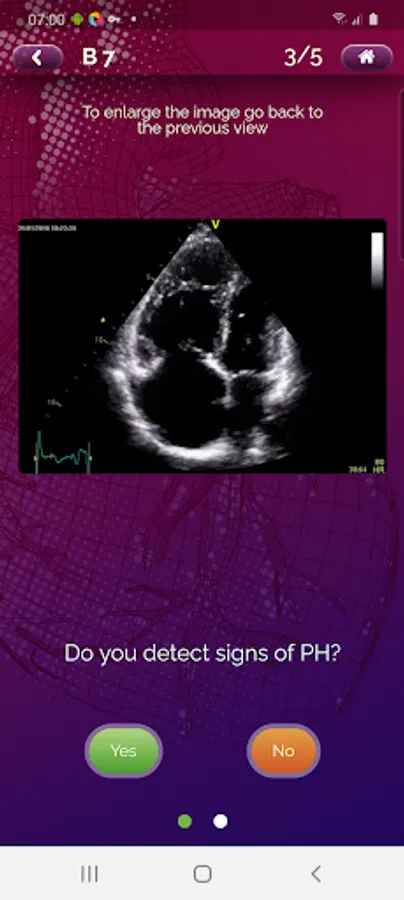

EchoRight Pro is an upgraded version of EchoRight created for cardiologists, echocardiographers, and sonographers to help learn the echocardiographic signs of pulmonary hypertension (PH).

EchoRight Pro is an advanced version of EchoRight enriched with additional cases, different levels of difficulty and pitfalls to address advanced learning objectives in cardiology.

• The key parameters for identifying the 8 PH signs and assessing the probability of PH